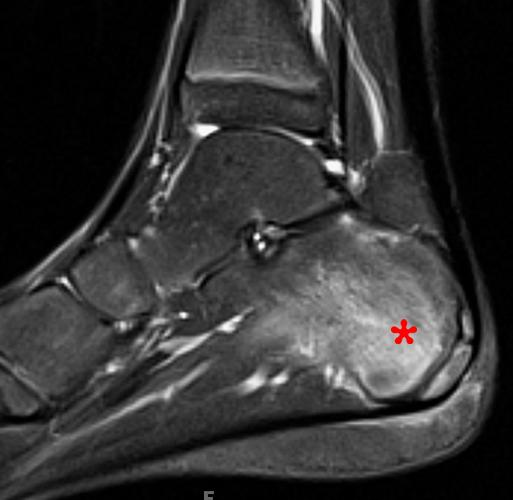

磁共振左足平扫增强

左足第一跖骨、第一足母趾近节趾骨、第一趾远节趾骨及第三趾中节趾骨多发异常信号灶,周围软组织肿胀,性质待定:炎症?请结合临床。

图B:患者趾骨水肿

MRI(金标准):T2加权像高信号(骨髓水肿),增强后强化,可发现早期无症状病灶。